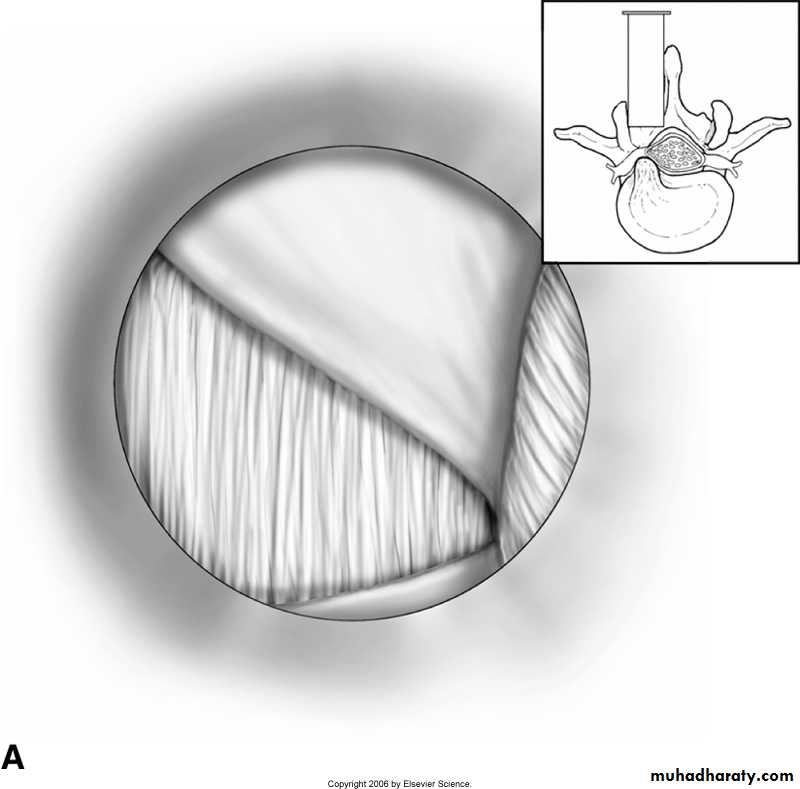

- open laminectomy with discectomy

- micro discectomy

Surgery